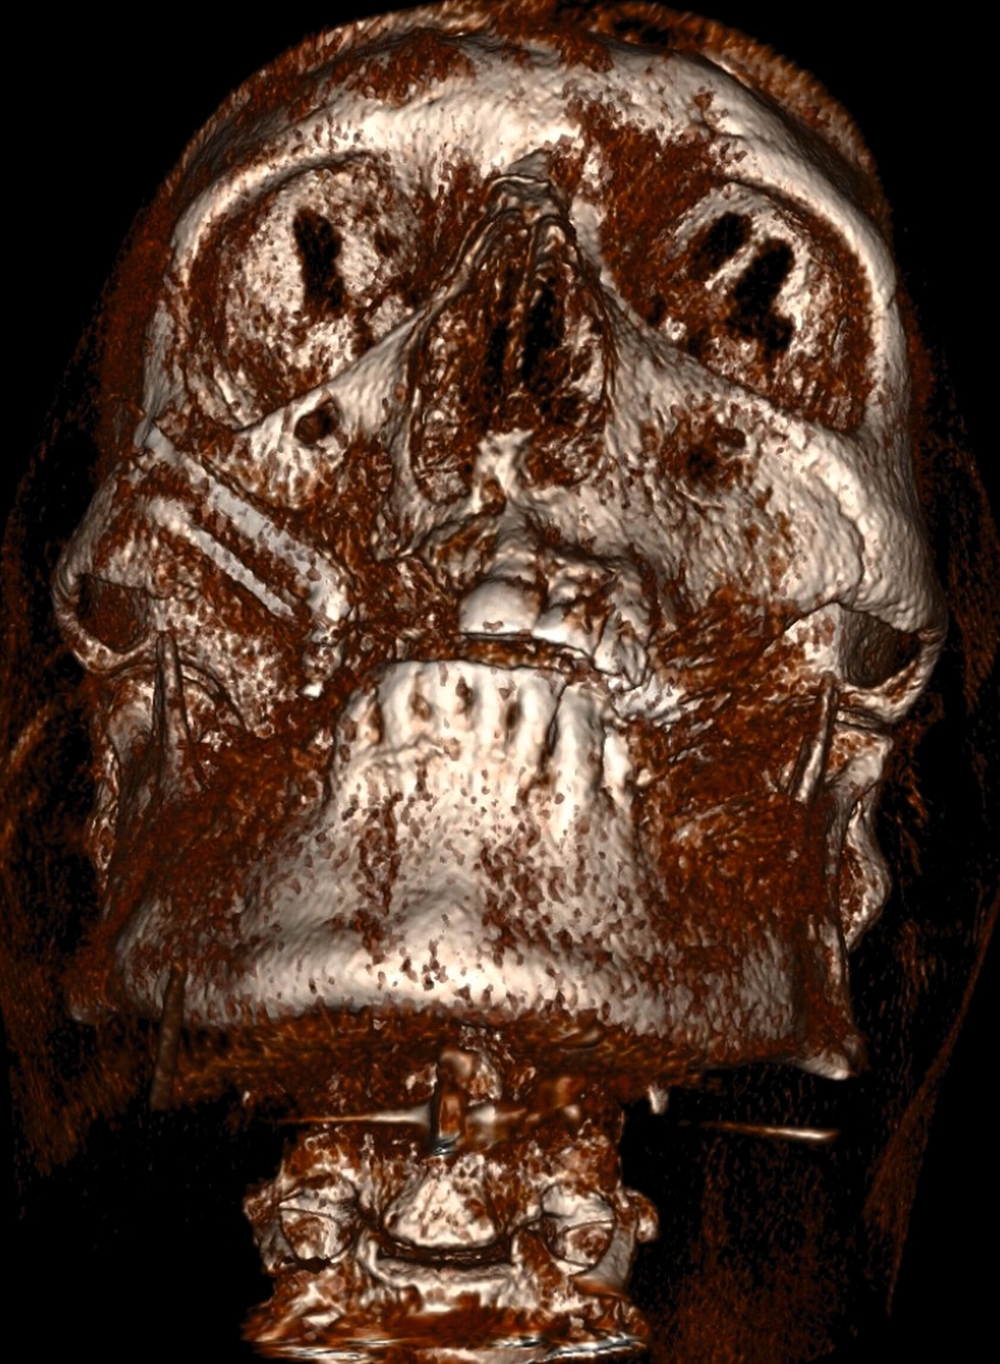

Zu Beginn der 2000er-Jahre setzten Bedrossian und Chow et al. Zygoma-Implantate zur Sofortbelastung erfolgreich ein und wiesen ausführlich auf die Vorteile für die betroffenen Patienten im Vergleich zu herkömmlichen Verfahren im Sinne einer Augmentation und anschließenden Implantatinsertion hin [Bedrossian et al., 2006; Chow et al., 2006]. Später wurde der klassische Zugang zum sogenannten „Quad-Ansatz“ weiter modifiziert. In diesem Kontext ist der Oberkiefer derart atrophiert, dass weder im anterioren noch im posterioren Bereich ausreichend Knochen für die Platzierung herkömmlicher Zahnimplantate vorliegt. Daher werden jeweils zwei Zygoma-Implantate pro Seite ins Jochbein inseriert [Davo und David, 2019] (Abbildung 3). Unter Verwendung dieser Technik wurde in der Literatur eine Überlebensrate der Implantate von 98 Prozent berechnet [Varghese et al., 2021].

Wenn es zu Implantatverlusten kommt, treten diese vor allem in der frühen postoperativen Phase auf [Chrcanovic et al., 2016]. Patienten, die mit Zygoma-Implantat-gestützten prothetischen Suprakonstruktionen rehabilitiert wurden, haben eine erhebliche verbesserte mundbezogene Lebensqualität und sind allgemein zufriedener im Vergleich zur präoperativen Situation [Saez-Alcaide et al., 2022] (Abbildung 4).